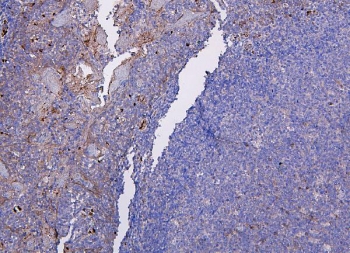

IHC staining of FFPE human tonsil tissue with CXCR2 antibody. HIER: boil tissue sections in pH8 EDTA for 20 min and allow to cool before testing.